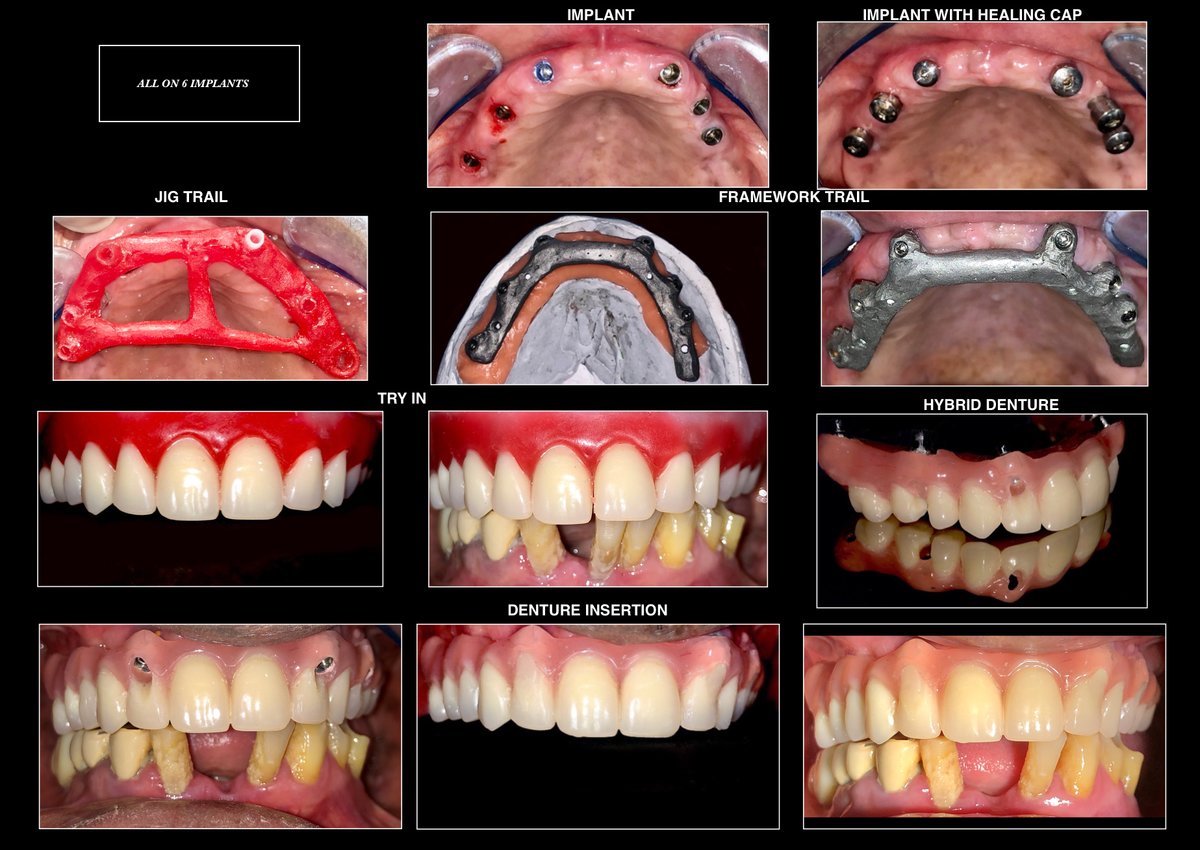

About Raga Dental Center for Dental Implants & Laser Raga Dental is a well established facility with experienced team of doctors , state of the art equipments and especially renowned for Implantology and waterlase Laser Dentistry. We are well equipped with Waterlase Laser, Navident for Navigation implant surgeries, 3D printer for Guided implant surgeries, Phillips zoom whitening for esthetic rehabilitation. We also excel in other ... (Show more)